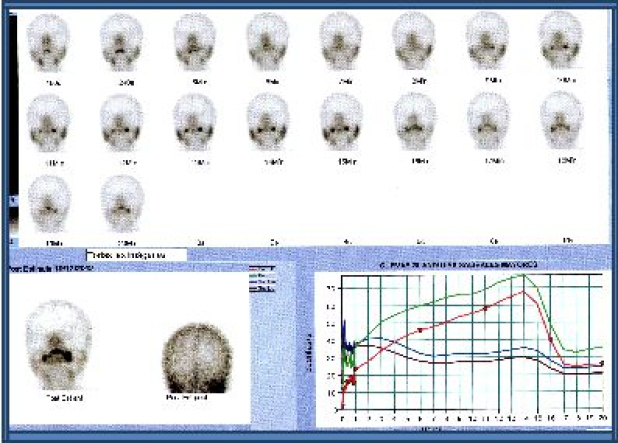

La función salival se estimó mediante la gammagrafía de glándulas salivales con administración endovenosa de 370 MBq (10 mCi) de 99mTc-pertecnetato. Los pacientes estuvieron en ayunas y fueron estudiados en posición decúbito supino, con una gammacámara de dos cabezales (Siemens E.cam, Hoffman Estates, EEUU). La adquisición fue realizada en modo dinámico en proyección AP en matriz 128x128 word a razón de 1 “frame” por minuto durante 60 minutos, incluyendo post estímulo con jugo de limón a los 15 min (21,23). Se construyeron cuatro regiones de interés ovaladas, posicionadas sobre las parótidas y submaxilares y se generaron curvas de actividad en función del tiempo (gráficas roja y verde correspondientes a las parótidas, marrón y verde a las submaxilares (21). Dependiendo de las características de captación y la excreción de las glándulas salivales, los pacientes se clasificaron en uno de cuatro patrones diferentes: Grado I, con captación y excreción normal (Fig. 1); Grado II, disfunción leve a moderada, caracterizada por disminución de la captación salival y retraso en la excreción, siendo la actividad oral igual en intensidad a la captación salival a los 60 min (Fig. 2); Grado III, disfunción moderada a severa, con marcada disminución de la captación de las glándulas salivales, excreción retardada y captación glandular mayor que la actividad oral a los 60 min; Grado IV, disfunción severa con disminución marcada de la captación glandular y la actividad de fondo más alta que la salival durante todo el estudio (22,23).